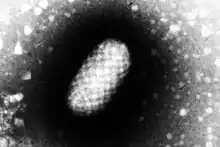

Orf virus